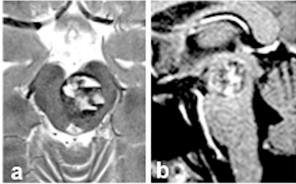

急救MRI的影像令人窒息:脑干再次出血,血肿有20mm大小(图a和b)。这一次医生不再建议保守治疗,但是医生仍表示脑干位置手术风险很大,稍有不慎可能瘫痪,除非有万全的把握,否则不会轻易手术。

图a和b:术前轴向(a)和矢状(b)MRI